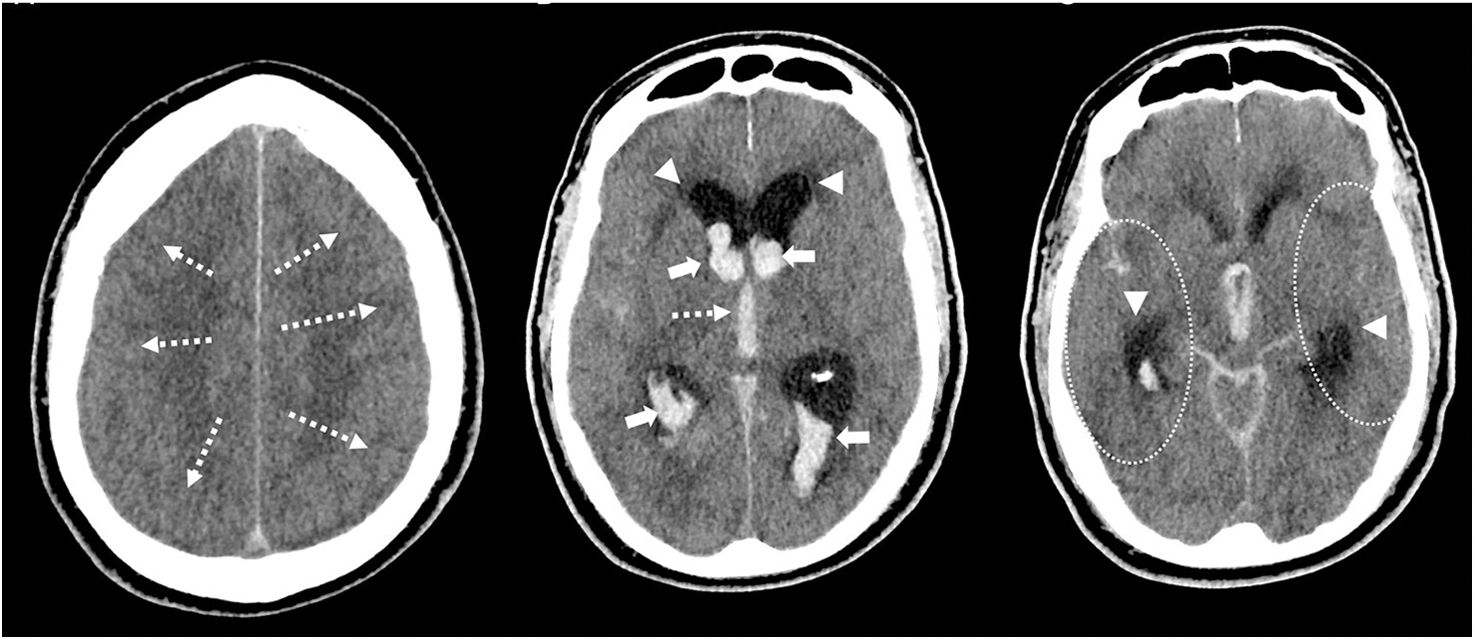

La hemorragia subaracnoidea espontánea (HSA) es una urgencia neurológica que afecta predominantemente a adultos jóvenes, con una elevada tasa de mortalidad y secuelas neurológicas graves en los supervivientes. Su manifestación clínica más característica es la cefalea súbita en trueno, considerada la peor cefalea de la vida, frecuentemente acompañada de alteraciones del nivel de conciencia y rigidez de nuca. La tomografía computarizada craneal sin contraste (TCCSC) constituye la herramienta diagnóstica inicial de elección, con alta sensibilidad. El reconocimiento de patrones de distribución del sangrado en la TCCSC permite orientar el diagnóstico etiológico y valorar la presencia de complicaciones como hidrocefalia, hemorragia intraventricular o edema cerebral. Esta primera parte del artículo proporciona una guía práctica y detallada basada en la imagen para el radiólogo en la fase hiperaguda de la HSA espontánea, diferenciando entre patrones aneurismáticos, perimesencefálicos y corticales, y discutiendo sus implicaciones clínicas, diagnósticas y terapéuticas.

Spontaneous subarachnoid haemorrhage (SAH) is a neurological emergency that predominantly affects young adults, with a high mortality rate and severe neurological sequelae in survivors. Its most characteristic clinical manifestation is a sudden thunderclap headache, often described as the worst headache of one's life, and frequently accompanied by altered levels of consciousness and neck stiffness. Non-contrast cranial computed tomography (NCCT) is the initial diagnostic tool of choice due to its high sensitivity. Recognising the distribution patterns of haemorrhage on NCCT helps guide the aetiological diagnosis and assess the presence of complications such as hydrocephalus, intraventricular haemorrhage or cerebral oedema. This article offers a practical and detailed imaging-based guide for radiologists in the hyperacute phase of spontaneous SAH, distinguishing between aneurysmal, perimesencephalic and cortical patterns, and discusses their clinical, diagnostic and therapeutic implications.